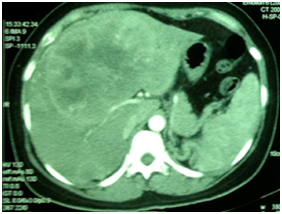

Presents jaundice to the physical examination. Abdomen was flaccid, flat painful to superficial and deep palpation in the epigastrium and right hypochondrium, being the liver palpable about 5 cm from the right costal edge. Laboratory tests performed, in which anemia was discovered, increase in the levels of TGO and TGP, increase in the direct and indirect bilirubin and Gama-GT. Serum tests for hepatitis reaching just for hepatitis A. USG demonstrates liver with its volume increased due to the presence of well-outlined mass hypoechogenic, heterogeneous, with areas of necrosis in its interior, with anechoic affecting the segments II, III, IV, VIII, with peripheral and central vascularization. It also demonstrated dilation of the intrahepatic biliary ducts (Figure 1).

Figure 1 USG demonstrates liver with its volume increased due to the presence of well outlined mass hypoechogenic, heterogeneous, with areas of necrosis in its interior, with anechoic affecting the segments II, III, IV, VIII.